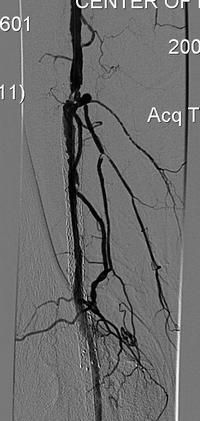

Пациент П, 1951 г.р. (56 лет).

- Атеросклероз.

- Окклюзия правой подколенной артерии и артерии правой голени.

- Сахарный диабет.

В мае 2007 г. произведена реканализация правой подколенной артерии, правого ТПС и правой ПББА со стентированием.

Тромбоз зоны стентирования в сентябре 2007 г.